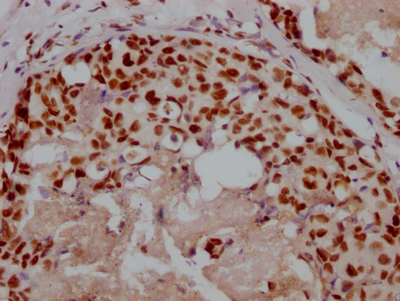

Immunohistochemistry of paraffin-embedded human lung tissue using CSB-PA001572EA01HU at dilution of 1:100